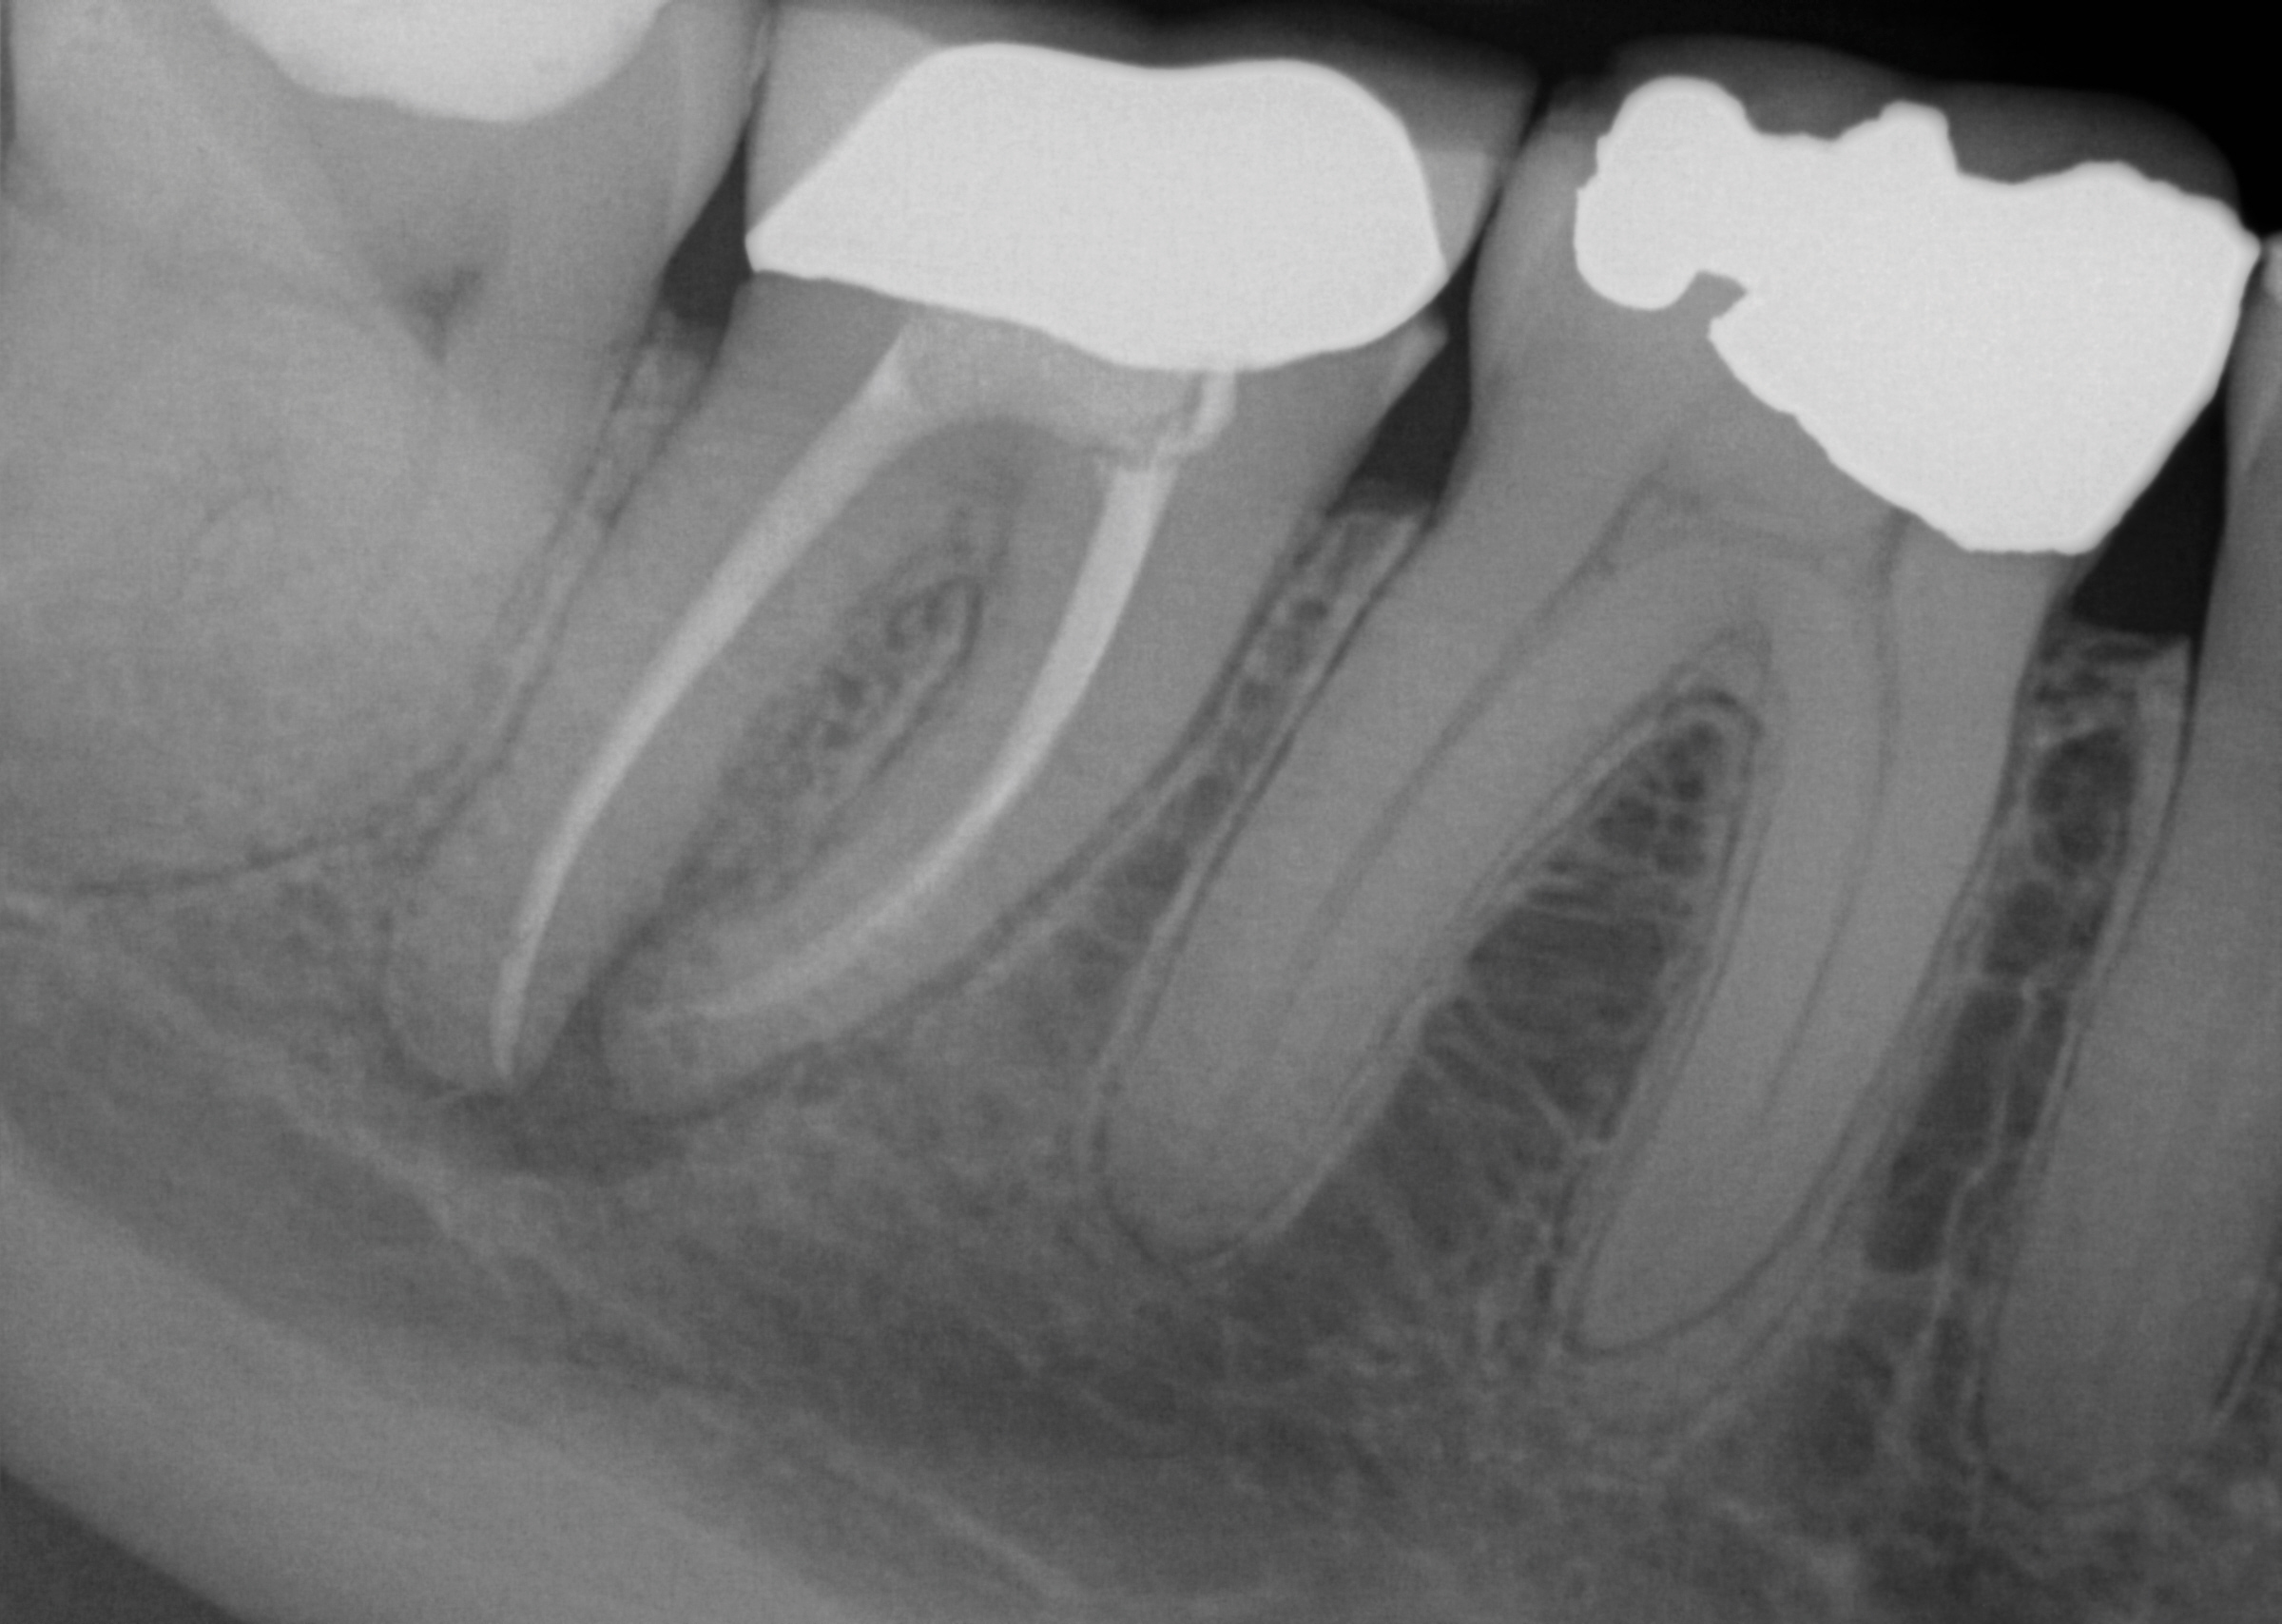

Fig 3. A patient presented with intense pain in tooth No. 31. A periapical radiograph demonstrated acute apical periodontitis. It was not possible to identify the extent of the periapical lesion with respect to the inferior alveolar canal.

Figure 3